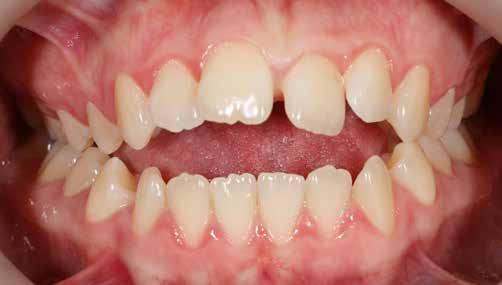

A fix fogszabályozó készülék mindössze 16 hónapos kezelés után került eltávolításra! Páciensünk legnagyobb örömére állcsontműtét nélkül sikerült mind az arcesztétikai, mind a funkcionális rehabilitáció (13–18. képek)